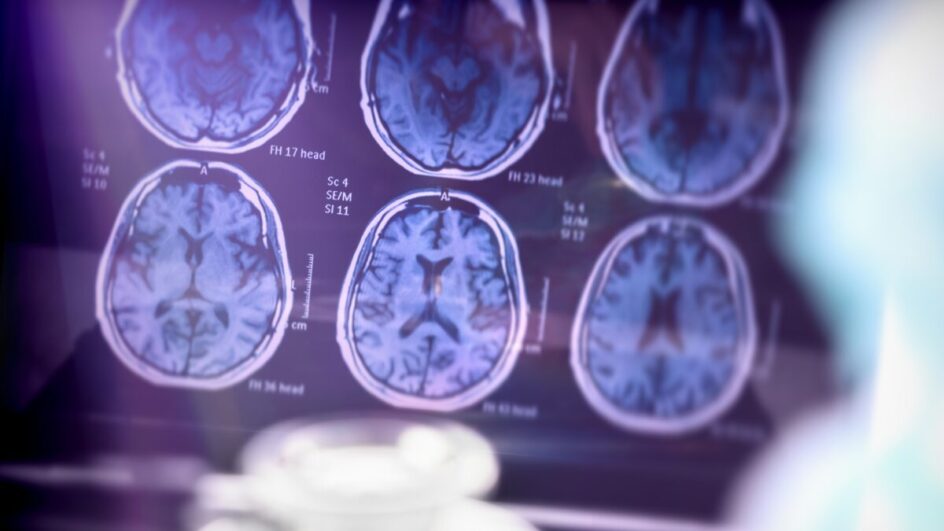

A doença de Alzheimer é uma condição neurodegenerativa progressiva que atinge a memória, o comportamento e a autonomia dos pacientes. Embora não haja cura, o tratamento pode contribuir para a redução do ritmo da perda de capacidades.